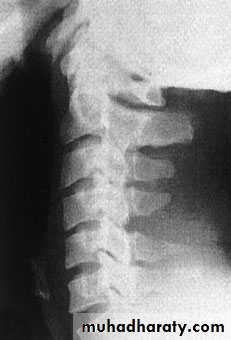

Wedge compression fracture

A pure flexion injury results in a wedge compressionfracture of the vertebral body .The middle

and posterior elements remain intact and the

injury is stable. All that is needed is a comfortable collar for 6–12 weeks.

. Diagnosis.

1. The x-ray should be carefully

examined to exclude damage to the middle column

and posterior displacement of the vertebral body

fragment, i.e. features of a burst fracture (see below)

which is potentially dangerous. If there is the least doubt

2. an axial CT

3. MRI should be obtained.